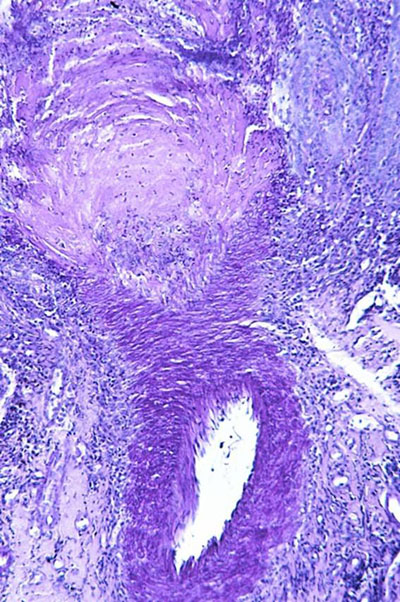

Photo 4 (réaction au PAS – X100) : au plancher de l’ulcère épidermique,

se trouve une artériole dermique à paroi musculaire épaisse.

Légendes de la Photo 4 :

- Pointes de flèches rouges = délimitation de l’ulcère épidermique.

- Etoile rouge = lumière vasculaire de l’artériole.

- Flèche double rouge = paroi musculaire de l’artériole (media).

Photo 5 (Hémalun-Eosine – X400) : vue rapprochée du plancher de l’ulcère épidermique,

permettant de visualiser la limitante élastique interne de l’artériole, sa media et son adventice.

Légendes de la Photo 5 :

- Flèche double rouge en pointillés = fond de l’ulcération épidermique, comblé par un exsudat fibrino-leucocytaire.

- Pointes de flèches rouges = elles indiquent une ligne acidophile onduleuse qui est la limitante élastique interne de l’artériole.

- Flèche double bleue = media de l’artériole.

- Etoiles rouges = infiltrat inflammatoire au sein de la media et de l’adventice du vaisseau sanguin artériolaire.